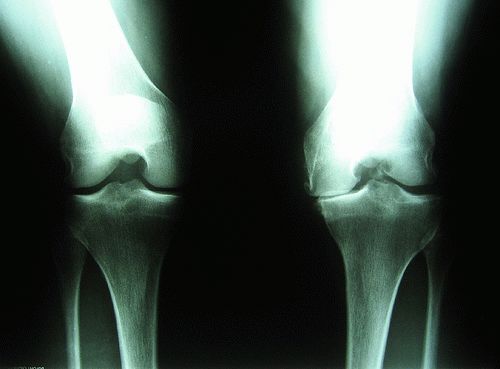

Болезнь чаще поражает крупные суставы. К специалистам обращаются пациенты, у которых диагностируется остеоартроз коленного сустава, который нередко формируется в результате бытовых и профессиональных травм. У пожилых людей на фоне остеопороза, нарушений обмена веществ и генетической предрасположенности может развиваться остеоартроз тазобедренного сустава, приводящий к инвалидизации и значительным двигательным ограничениям в будущем. Люди пенсионного возраста в группе риска по развитию опорно-двигательных нарушений. После 60 лет у большинства из них развивается остеопороз и остеоартроз кистей рук и других крупных суставов.

На рентгенограммах тазобедренный сустав сохраняет нормальную форму, суставная щель умеренно или неравномерно сужена с субхондральным склерозированием костных суставных поверхностей, непостоянными краевыми костными разрастаниями (I стадия).

Рентгенологически суставная щель может быть равномерно или неравномерно сужена, ацетабулярная суставная впадина уплощена, присутствуют явления субхондрального склероза, краевые костные разрастания. Конфигурация головки бедренной кости, как правило, не нарушена (II стадия).

В подавляющем большинстве случаев диагноз коксартроза ставится при рентгенографии, где видны изменения формы и структуры костей, составляющих тазобедренный сустав. Однако рентгенографически в ряде случаев затруднительно зафиксировать ранние проявления артроза, так как хрящевая ткань суставных поверхностей на рентгеновских снимках не отображается и мы можем судить о дегенеративном процессе, когда он достаточно выражен, вызывая изменения ширины просвета рентгеновской суставной щели.